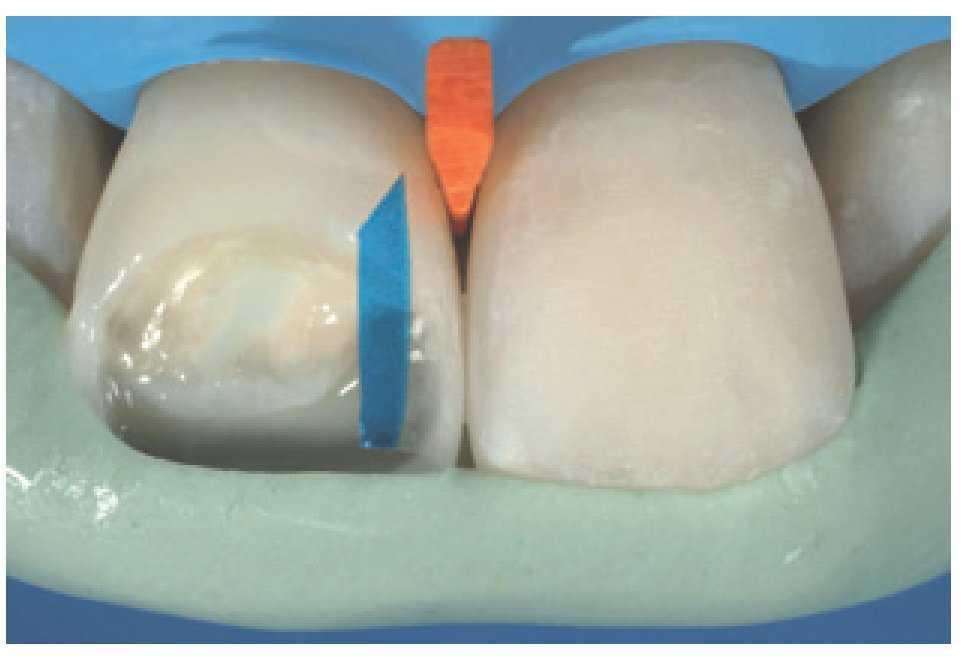

Esto es una ayuda importante, ya que consigue que el trabajo sea predecible, permite gestionar bien el tiempo y limita el tiempo de trabajo en el sillón. Asimismo, las matrices transparentes seccionales con múltiples convexidades (KerrHawe, Bioggio, Suiza) también son una ayuda útil en el manejo del tiempo, ya que permiten al clínico crear de forma sencilla e intuitiva unos perfiles de emergencia correctos. Éstas son las herramientas para gestionar de forma correcta la configuración de las restauraciones, eliminando cualquier exceso de material que conllevaría intervenciones de remodelado laboriosas y difíciles, con el riesgo añadido de dañar los dientes adyacentes y perder los puntos de contacto. Una matriz seccional es un medio útil para restaurar la anatomía interproximal gracias a su elasticidad intrínseca, que hace que sea altamente adaptable a un gran número de morfologías dentales (figuras 38 y 39). Asimismo, ayuda a evitar la contaminación accidental de los dientes adyacentes durante las fases de grabado y adhesión (figura 40). La aplicación combinada de una llave estable y matrices seccionales permite al clínico manejar de forma sencilla e intuitiva incluso las formas dentales más complejas en un único paso, optimizando así tanto el tiempo de trabajo como el resultado final (figuras 41-44).

Figura 38 Uso de una matriz seccional transparente para restaurar los perfiles de emergencia y puntos de contacto correctos.

Figura 39 Paso de estratificación, cavidad de clase III en diente número 22.

Figura 40 Uso de la matriz seccional durante la fase de grabado de la cavidad para evitar la contaminación de los elementos adyacentes.

Figura 41 Uso combinado de la llave de silicona y la matriz seccional para «encofrar» al mismo tiempo en palatino e interproximal.